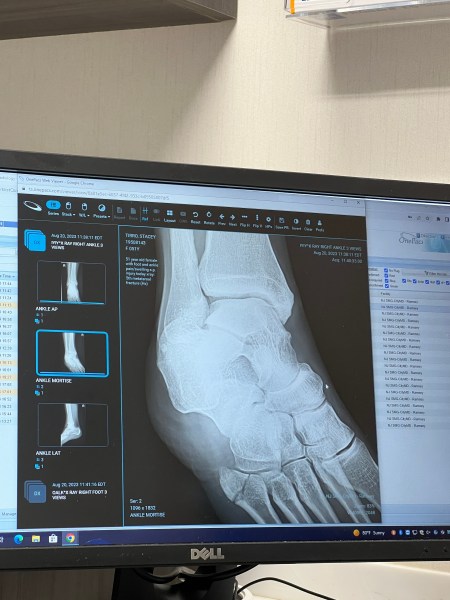

Long story short, the snap was a break of the 5th metatarsal (pinky toe side of the foot). You can see the crack in the end of the bone at the mid foot. The urgent care PA said the word “crushed.” 😩😩😩.